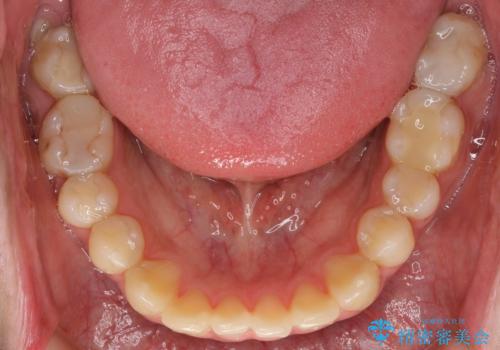

憧れの芸能人のような白い歯に 30代男性

- 憧れの芸能人(ヴィジュアル系バンドマン)のような歯になりたいとのご希望で来院された患者様です。

咬み合わせが悪く矯正も検討されていたそうですが、歯を真っ白にしたいというご希望もあり、28本のすべての歯をセラミックにしたいとのことでした。

精査したところ、ほとんどの歯が保険内のレジンで充填されており、咬み合わせも悪く咬合していない歯もありました。

虫歯をしっかりと治療したのち、オールセラミッククラウンによる補綴治療を行いました。

憧れのヴィジュアル系バンドマンのような白い歯になり、喜んで下さいました。

不適なレジン充填によるデコボコがなくなったことで歯磨きしやすくなり、また気にされていた咬み合わせも良くなり、ご満足頂けました。

クラウンの種類:オールセラミッククラウン スタンダード

シェード:NW0